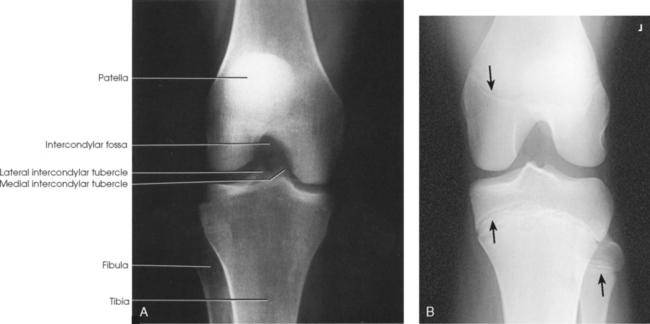

Structures shown: The resulting image shows an AP projection of the knee structures (Fig. 6-121).

Structures shown: The image shows the intercondylar fossa of the femur and the medial and lateral intercondylar tubercles of the intercondylar eminence in profile (Fig. 6-139). Holmblad1 stated that the degree of flexion used in this position widens the joint space between the femur and tibia and gives an improved image of the joint and the surfaces of the tibia and femur.

Structures shown: This axial image shows an unobstructed projection of the intercondyloid fossa and the medial and lateral intercondylar tubercles of the intercondylar eminence (Figs. 6-142 and 6-143).

Fig. 6-142 Camp-Coventry method. A, Flexion of knee at 40 degrees. B, Flexion of knee at 40 degrees in a 13-year-old patient. Note epiphyses (arrows).

Fig. 6-143 Flexion of knee at 50 degrees (same patient as in Fig. 6-142): Camp-Coventry method.